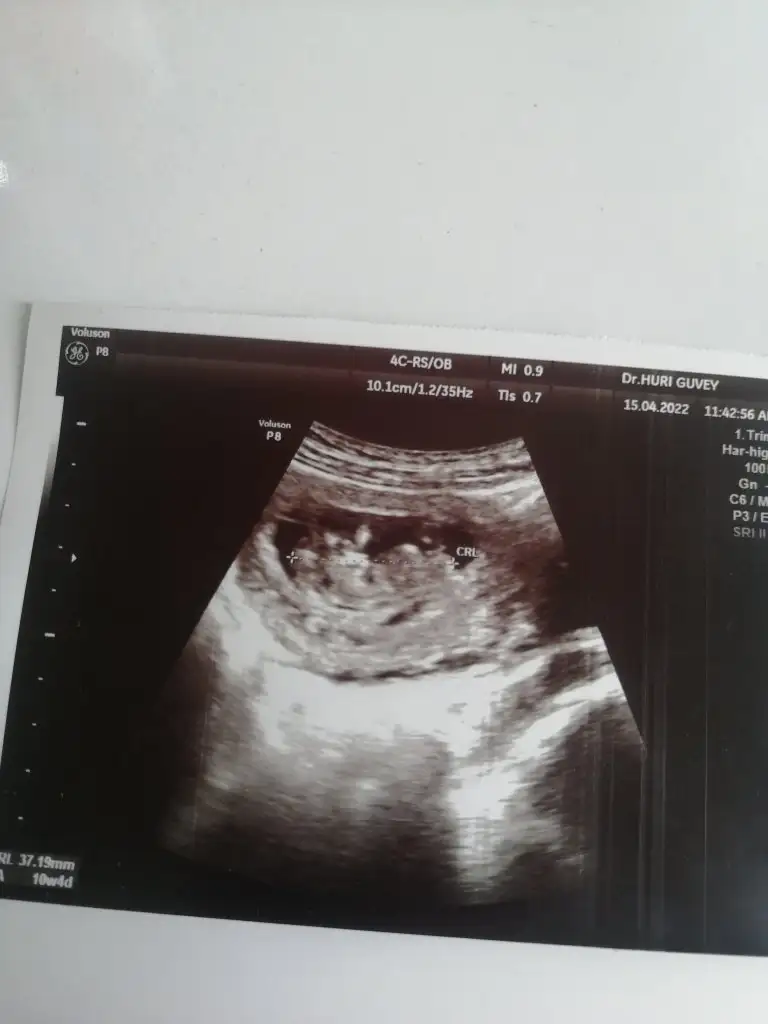

5 ve 14. haftaya kadar olan ultrason fotolarınızı paylaşın. Vajinadan mı yoksa karından mı çekildiğini ve kaç haftalık olduğunu da mutlaka belirtin.

simsiyah bir görüntü canım maalesef belli olmuyor10 hafta karindan tahmin edermisin canim